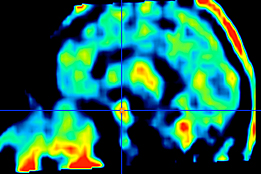

Ce projet, en collaboration avec l’EPFL (Laboratoire LTS-5 du Prof. Thiran), étudie plus particulièrement à la thalamotomie par Gamma Knife du noyau Vim du thalamus pour le tremblement essentielement de la maladie de Parkinson, comme alternative à la stimulation cérébrale profonde (DBS). Ses objectifs sont, d’une part, d’améliorer le ciblage, en développant de nouveaux algorithmes basés sur l’acquisition et de processing d’images IRM; d’autre part, de mieux comprendre l’effet thérapeutique de la radiochirurgie, par l’étude longitudinale par IRM de la connectivité fonctionnelle du Vim.